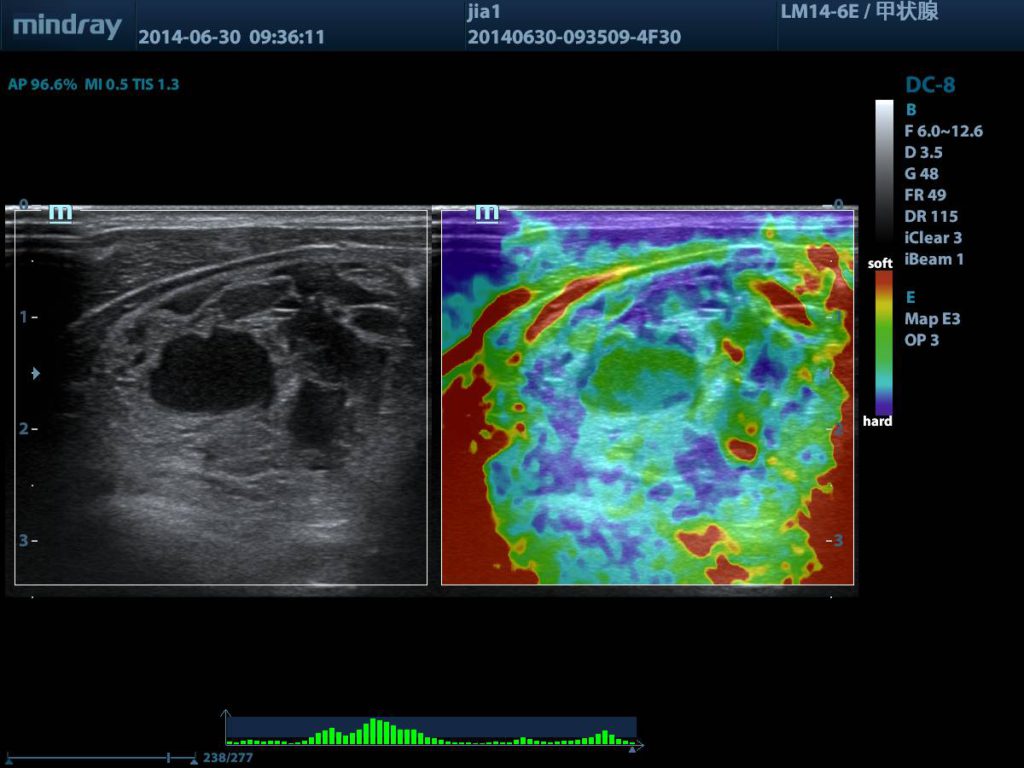

Thyroid Tumor with Elastography